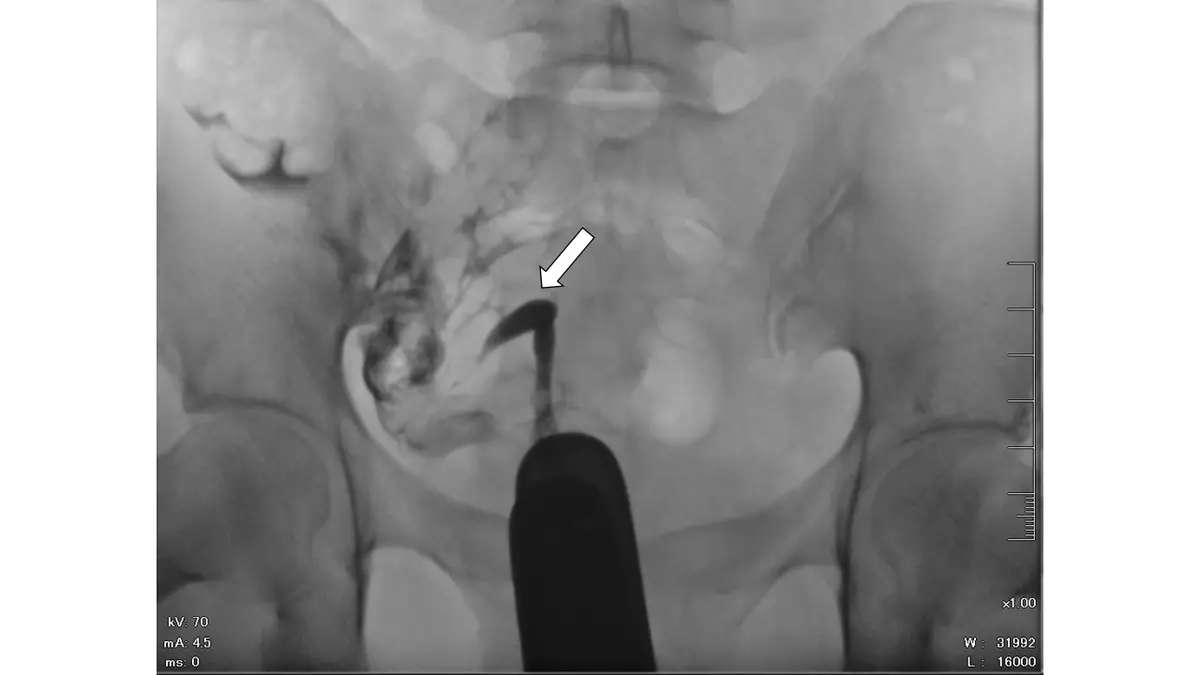

32 歲女性,子宮輸卵管攝影檢查呈現如圖,箭號所指之敘述何者最正確?

本圖為骨盆腔 X 光片,顯示子宮輸卵管攝影的影像(拍攝條件:70 kV, 4.5 mA)。圖中可見造影劑充填子宮腔的影像,白色箭號指向子宮腔輪廓。

- 子宮腔形態:呈現單一、細長呈香蕉形(banana-shaped)或梭形(fusiform)的腔室,整體偏向骨盆腔左側

- 腔室不對稱:只見一側子宮角(uterine horn),對側(右側)缺乏對應的子宮角結構,無正常的倒梯形(triangular)子宮底輪廓

- 輸卵管:僅能辨識單側輸卵管,與單角子宮的特徵一致

- 子宮腔大小:整體腔室較正常子宮為小

- 造影劑分佈:子宮腔及部分輸卵管顯影,造影劑向腹腔溢出(peritoneal spill),提示至少一側輸卵管通暢

上述影像特徵——單側偏斜的小型梭形子宮腔、僅單側輸卵管顯影——是單角子宮在 HSG 上的典型表現。